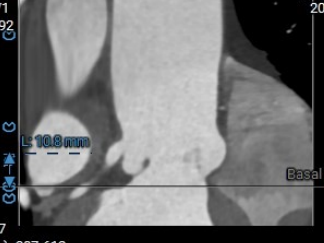

术前CT评估:三叶瓣,无钙化,瓣叶情况好,下肢动脉情况好。

主动脉瓣环直径25.8

瓣环上2 27.3

瓣环上4 27.3

LVOT

SOV

STJ

左冠高度10.8

右冠高度12.6

主动脉瓣环角度38°

舒张期瓣环直径25.3

舒张期瓣环2直径29.5

外周血管入路